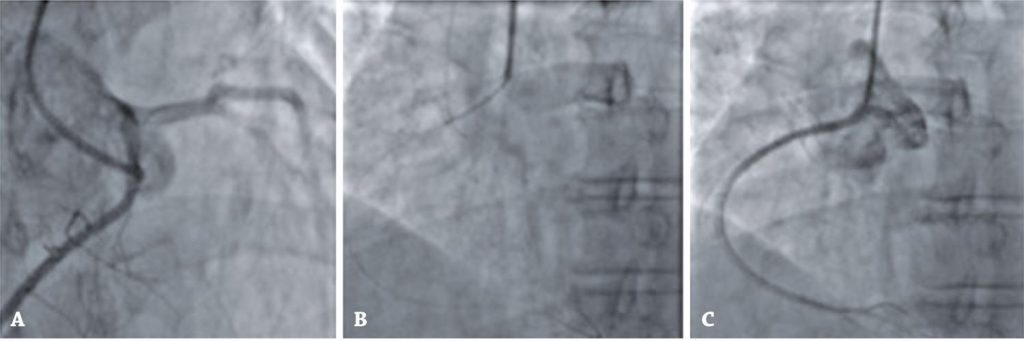

Figura 10

Imagens da angiografia de coronárias ilustrativas do caso 3. (A) Artéria coronária direita originando-se do seio coronário esquerdo. (B) Implante de stent farmacológico em coronária direita proximal. (C) Resultado angiográfico pós-tratamento.